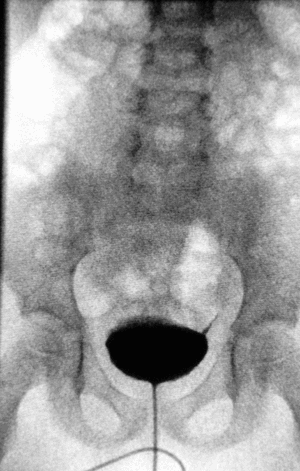

Урографія

Урографія — метод рентгенологічного дослідження нирок і сечових шляхів після внутрішньовенного введення рентгеноконтрастної речовини[1].